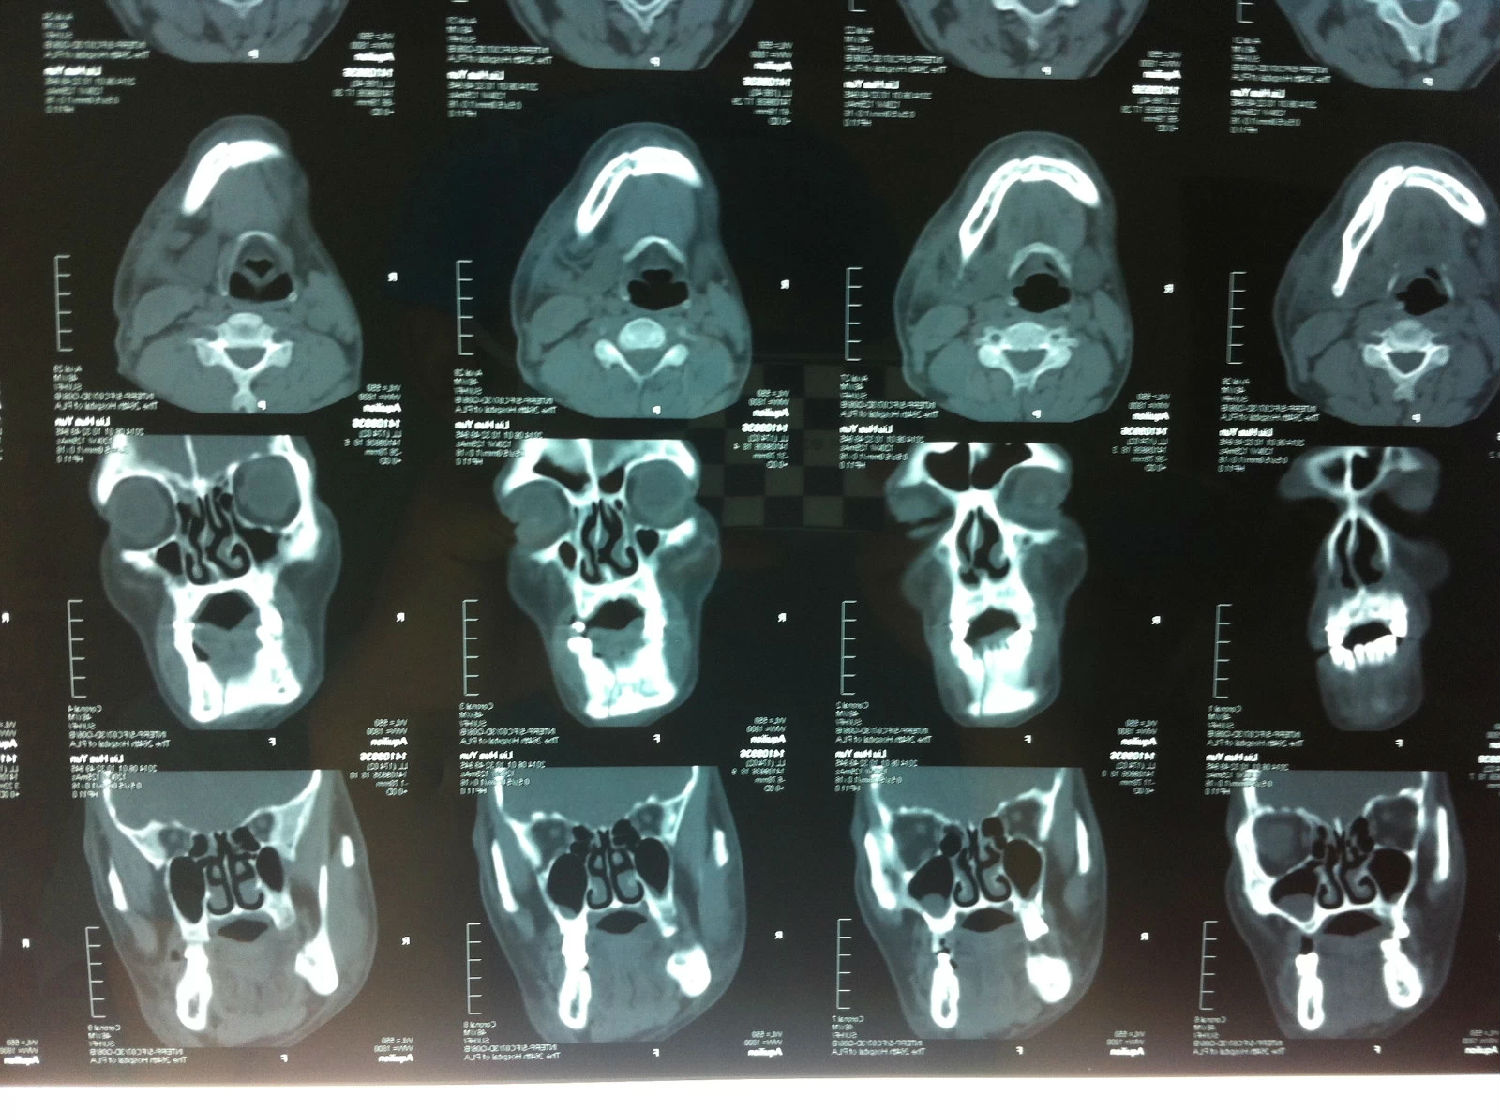

多發(fā)性頜骨囊腫綜合征一例

患者男性,主因左面部反復(fù)腫脹半年余,就診后行全景片檢查,發(fā)現(xiàn)下頜骨多發(fā)性囊腫,初步診斷為多發(fā)性頜骨囊腫綜合征,安排住院手術(shù)。

入院后全麻下手術(shù)治療,左側(cè)下頜骨囊腫較大,術(shù)前考慮病理性骨折可能,準(zhǔn)備鈦釘鈦板固定,術(shù)中摘除囊腫后,發(fā)現(xiàn)下頜骨下緣骨量尚可,未給予固定。術(shù)后病理診斷為下頜骨角化囊腫,考慮到患者可能為基底細(xì)胞癌綜合征,術(shù)中切除頸部皮膚痣兩處,術(shù)后病理診斷為:皮膚痣,排除基底細(xì)胞癌綜合征。患者有左側(cè)第六肋骨分叉肋,綜合以上特征,最終診斷為多發(fā)性頜骨囊腫綜合征。